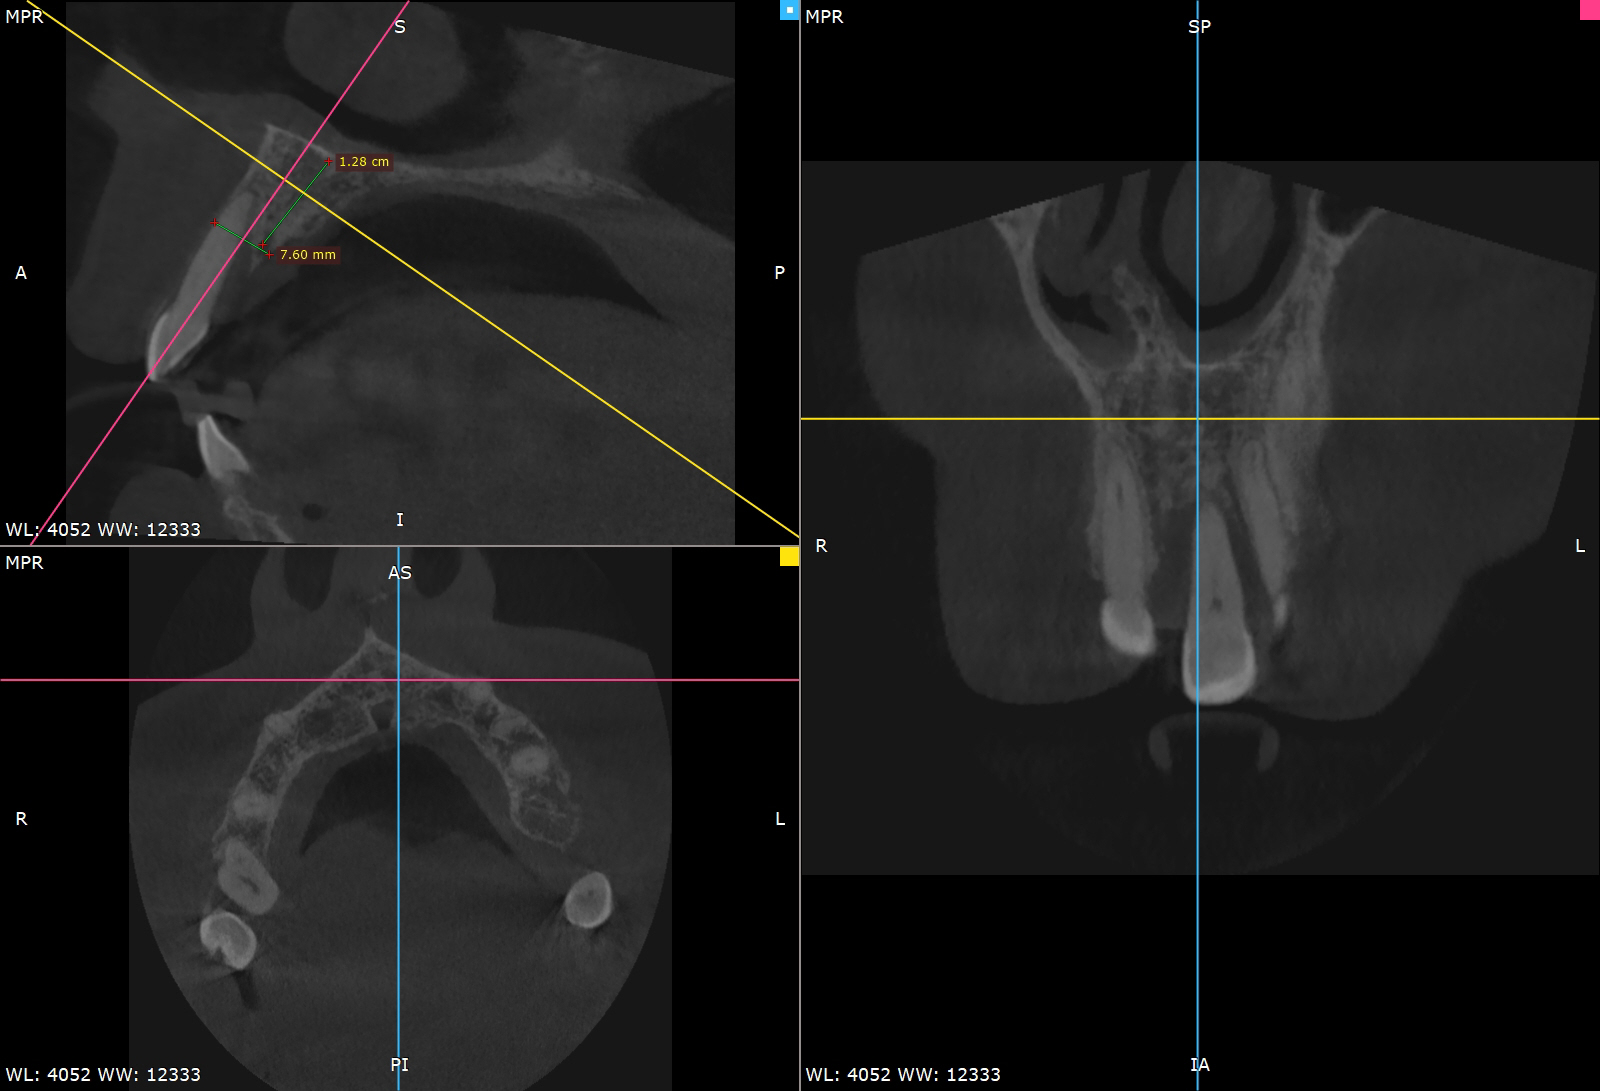

Pre-operative planning was performed using the DICOMLAB digital planning platform. The workflow included a pre-operative CBCT scan of the upper jaw and a digitalintraoral scan.

These datasets were merged within the DICOMLAB software to allow prosthetically driven implant planning.

Planned implant:

DSI Conical Implant - 4.3 mm diameter, 13 mm length.

A custom surgical guide was fabricated using the DICOMLAB open platform, which allows surgical guide production for most implant systems.

The DICOMLAB surgical guide was positioned, and the implant was placed according to the digital plan.

Implant placed: DSI Conical Implant – 4.3 × 13 mm.

Primary stability achieved: 45 Ncm insertion torque.

Achieving this level of stability and ideal prosthetic positioning would have been extremely difficult without guided surgery due to the severe buccal bone deficiency.